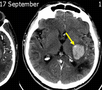

[ISC2017]新型神经影像征:血管里的「炸油条」